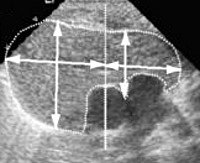

Нормальный тимус - это орган со средней эхогенностью, гладкими контурами и однородной структурой. Железа четко ограничена другими анатомическими структурами и мягкими тканями переднего средостения. Задний край тела плоский. При наличии опухолей вилочковой железы при УЗИ выявлены участки с измененной эхогенностью, неоднородностью структуры, изменением размеров и формы железы. При синдроме Ди Джорджи определяется аплазия тимуса, при миастении - у некоторых пациентов тимома.

Для более точной оценки расчеты выполняются с использованием данных о массе, длине, ширине и толщине фракций органов, полученных во время УЗИ. На их основе рассчитывают объем и массу каждого волка, а также общий объем и массу железы. На заключительном этапе определяется торический индекс - масса вилочковой железы делится на массу тела ребенка, а затем полученное число умножается на 100%. Химический индекс сравнивается с показателями в специальной таблице. Нормальная масса вилочковой железы должна составлять 0,3% от массы тела ребенка. При увеличении этого показателя говорят о тимомегалии, при уменьшении - по неравенству в размерах железы вплоть до возраста ребенка. Результаты УЗИ вилочковой железы следует направлять к педиатру, врачу общей практики или иммунологу.